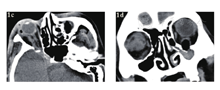

急诊入院者16例,均行眼眶CT检查,其中6例患者发现异物影(37.5%),发现异物影者主要为铅笔或筷子类异物(图1a、b),而竹子类异物较难发现,多表现为絮状密度影等感染征象、不能显示明显异物影(图1c、d);早期入院者7例,均行眼眶CT检查,其中4例发现异物影(57.1%),表现为条状或片状低密度影,周围伴软组织密度影(图2);中晚期入院者19例,4例在外院行了眼眶CT外余均在我院行眼眶CT检查,其中16例扫描表现为高密度条索状或片状异物影(84.2%),大部分能显出异物大致轮廓,周围多伴有软组织密度影(图3)。